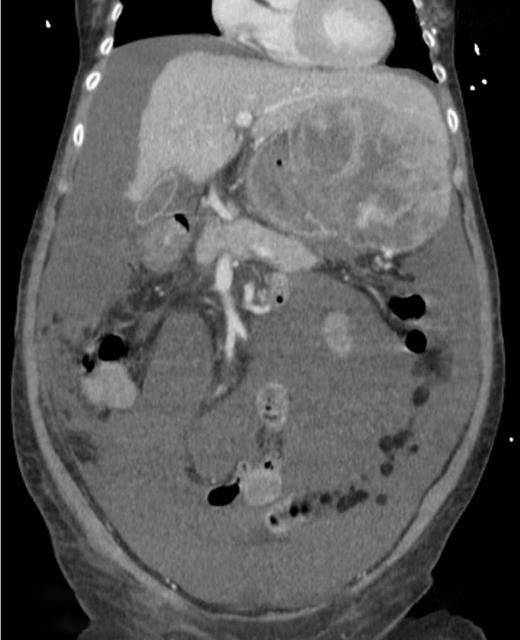

A computed tomography scan was performed which showed multifocal HCC with a large exophytic lesion invading into the greater curvature of the stomach (Figs. 3 and 4). Peritoneal metastases and ascites were present. The patient underwent an angioembolization of the hepatic tumour on the same evening. Angiography identified a replaced left hepatic artery as the dominant vessel supplying the lesion of concern in the left lateral hepatic segment (Fig. 5a). Gelfoam embolization was performed with no residual tumour enhancement thereafter (Fig. 5b).

Computed tomography image showing HCC invading into greater curvature of stomach.

Computed tomography image showing tumour originating from the liver.